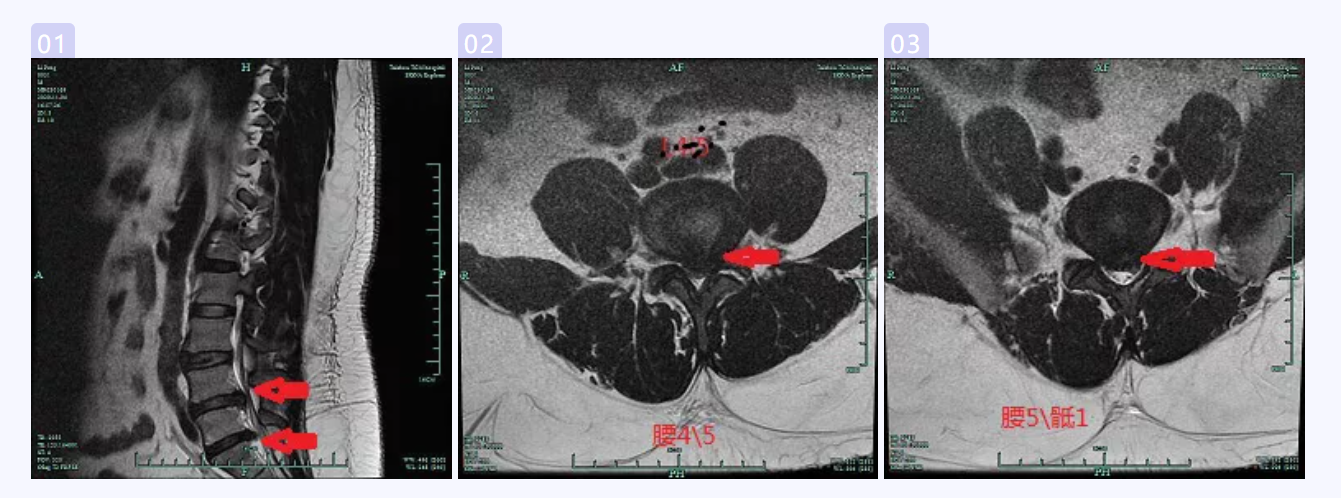

患者李某,31歲男性,家住路橋區(qū),挖掘機駕駛員,已經(jīng)被“腰椎間盤突出癥”折磨了6年,腰腿痛得已經(jīng)無法正常行走,跛行明顯。而這個病例的特別之處,并不是患者病程長,而是患者身高172cm,體重卻有252斤?;颊咦栽V自己之前一直口服中藥、針灸推拿等,病情也是時輕時重。住院前2天因為勞累后導(dǎo)致腰痛伴左下肢放射性麻痛明顯,根本無法行走,在家臥床休息時剛好電視上在播放《阿福講健康》,欄目中顏峰副主任中醫(yī)師在講述“椎間孔鏡技術(shù)治療腰椎間盤突出癥”,患者被案例中的神奇療效所吸引。遂于2020年11月4日到顏峰副主任中醫(yī)師門診就診,經(jīng)仔細詢問病史查體后,考慮“腰椎間盤突出癥”,為了進一步了解病情,建議患者行腰椎MRI、CT檢查,檢查結(jié)果(見下圖)提示腰4/5、腰5/骶1椎間盤突出明顯,神經(jīng)根明顯受壓,且由于突出時間長,突出的髓核嚴重鈣化。

腰椎MR

腰椎間盤CT

經(jīng)過科室內(nèi)討論,一致認為患者癥狀體征與影像學(xué)表現(xiàn)相符,符合手術(shù)指征??紤]到患者的體重、雙節(jié)段突出及髓核鈣化等因素,使得手術(shù)的難度、手術(shù)時間都大大增加,在與患者及家屬充分溝通后,擬行“椎間孔鏡下腰4/5、腰5/骶1椎間盤突出髓核摘除術(shù)”。入院完善術(shù)前檢查及術(shù)前準備后,于2020年11月6日在局麻下由顏峰副主任中醫(yī)師主刀行“椎間孔鏡下腰4/5、腰5/骶1椎間盤突出髓核摘除術(shù)”,術(shù)中進展順利,在對神經(jīng)根減壓松解充分后,患者腰腿痛即刻緩解。